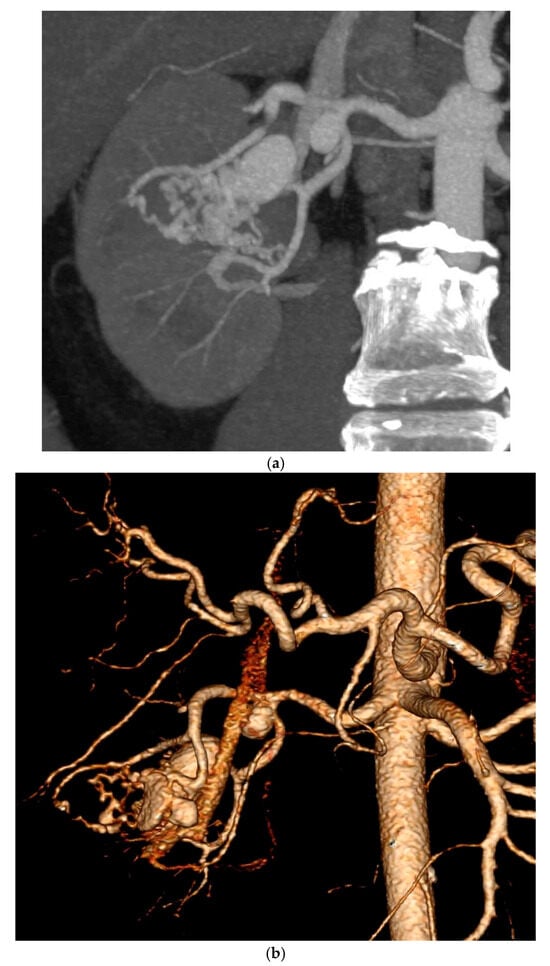

CT urography revealed a 26 × 16 mm aneurysm of the right renal artery and two smaller aneurysms in the same vessel, together with a prominent vascular arborization in the upper pole, suggestive of an AVM. The right kidney demonstrated reduced contrast secretion and excretion, while the left kidney appeared normal. Ultrasound performed on admission confirmed an enlarged right kidney with a dilated pelvicalyceal system and microcalculi.

During hospitalization, he received antibiotics and underwent cystoscopy with evacuation of bladder clots. CT angiography confirmed the AVM (Figure 1a) and selective angioembolization was performed via a left femoral approach (Figure 1b). Post-procedure angiography demonstrated complete occlusion of the AVM nidus (Figure 2a) with preserved perfusion of the remaining renal vasculature (Figure 2b). At discharge, he was clinically stable, with normalized creatinine and clear urine. The administered therapy during hospitalization and subsequent follow-up is outlined in Table 2. After discharge, the patient was prescribed fosinopril (Monopril) 10 mg twice daily, titrated to the maximally tolerated dose and empagliflozin 10 mg once daily. Follow-up visits were scheduled at 6 and 12 months after embolization as determined by the attending nephrologist, consistent with routine monitoring intervals for renal recovery and therapy adjustment in clinically stable patients.

Figure 1. (a) Maximum intensity projection, axial plane of CT renal angiography in arterial phase, showing aneurysmal dilatation of a segmental branch of the right renal artery with early opacification of the renal vein, suggestive of arteriovenous malformation. (b) Selective renal angiography confirming the presence of a large AVM. Selective cannulation of arterial feeders was performed using a Rebar-18 microcatheter (Medtronic/EV3 Neurovascular—Irvine, California, USA), followed by coil placement and Onyx-18/34 glue embolization of the AVM nidus.